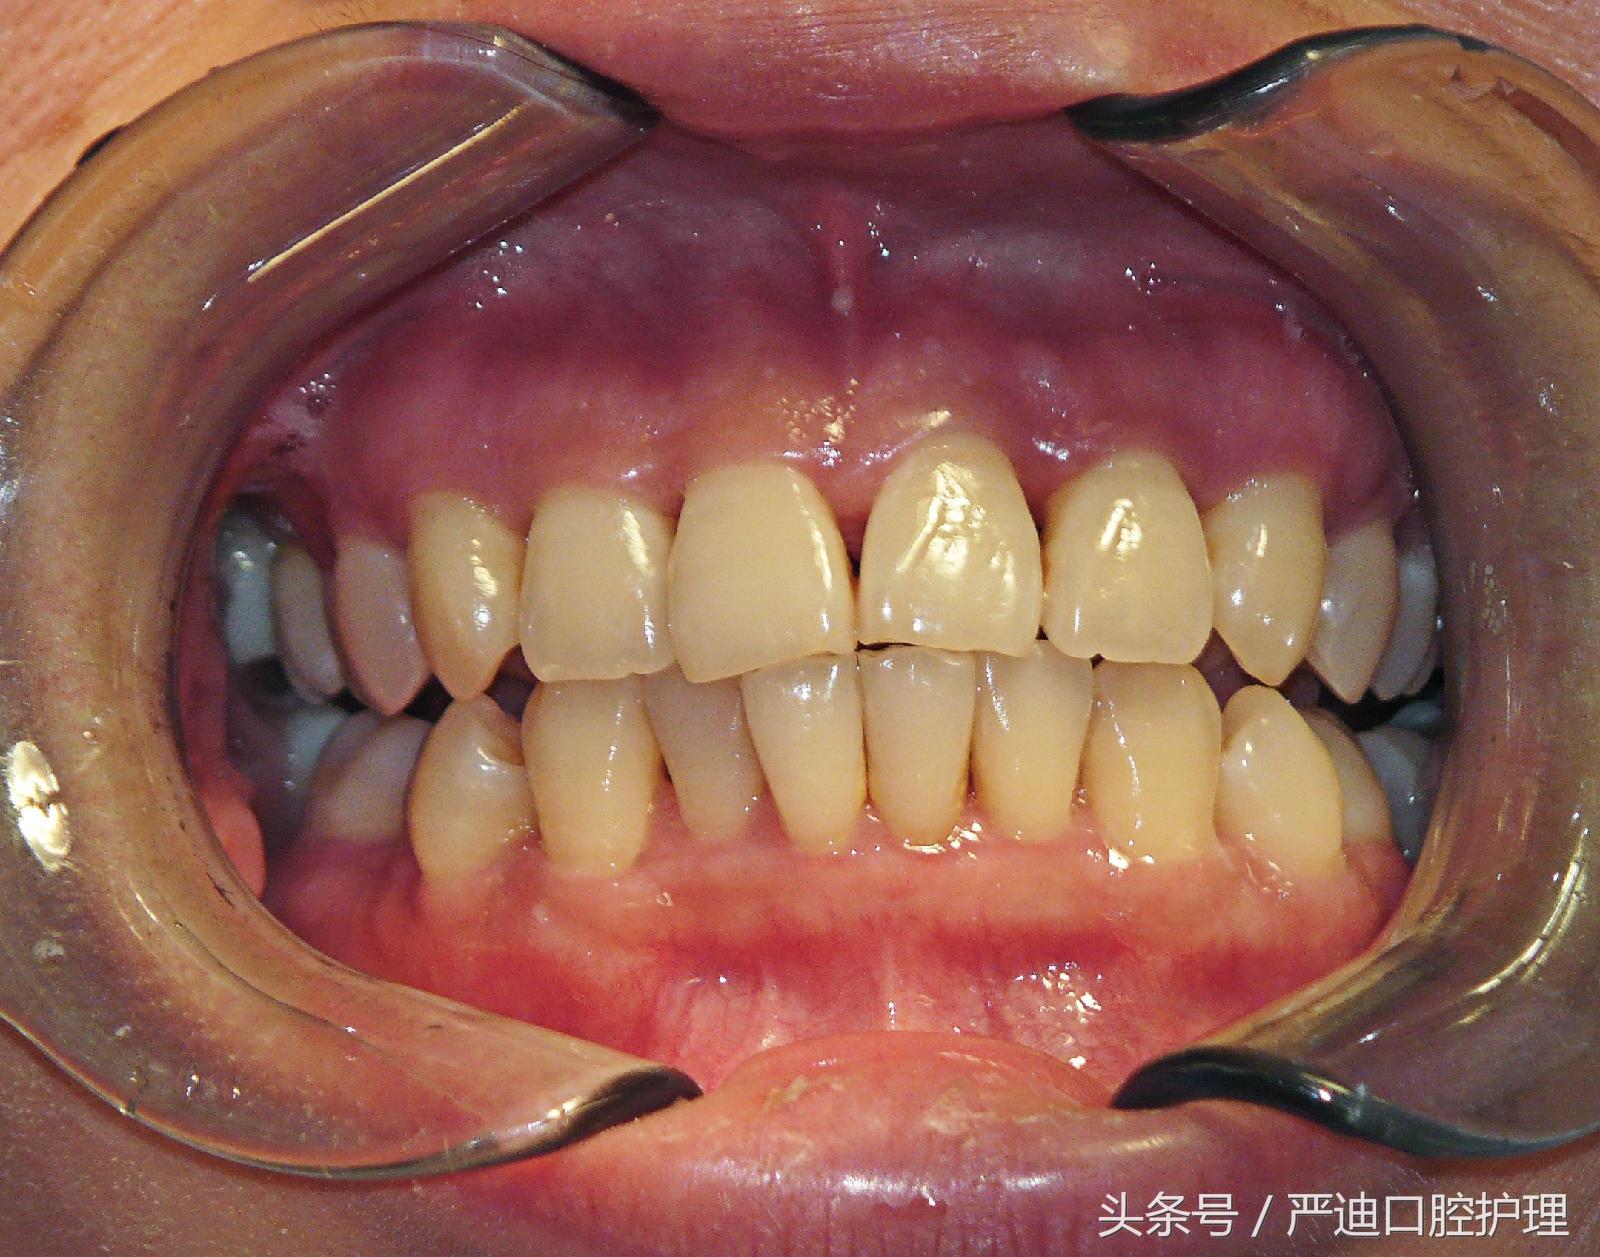

前沿拓展:牙齒矯正黑三角是什么

黑三角是個(gè)什么東東呢?

一般人的牙齦是能夠完全覆蓋兩個(gè)牙齒的牙頸部與接觸點(diǎn)間的縫隙的。

當(dāng)出現(xiàn)不能完全覆蓋的情況,就會(huì)形成一個(gè)黑色的,鏤空的三角形。它就是黑三角。